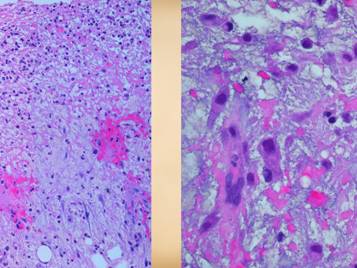

When hypercoagulable patients present with chronic ulcers, some of their histories can be otherwise quite benign.  The wounds and their treatment can be slow, subtle, persistent, recurring, frustrating, refractory, but a patient’s general health and well-being are not in any immediate jeopardy – or are they?  Some such patients have histories of serious prior events, such as blindness due to retinal artery occlusion, strokes, limb loss from trauma, recurrent pulmonary “emboli”, and other macro-vascular events.  All hypercoagulable patients have these potential risks.  With the appropriate trigger or generalized inflammatory or hyper-thrombotic state, even the micro-vascular events can become extensive and life-threatening.  This slide shows three patients who died from these conditions.  Left upper:  this patient had heart surgery, and a week or two after starting warfarin, he developed multiple non-embolic skin and extremity infarcts.  Peripheral arteries were normal.  Lab studies confirmed low APC resistance and probable factor V abnormality.  The events were non-survivable.  Lower:  this patient had sigmoid resection for a diverticular colo-vesical fistula.  Bowel necrosis resulted in progressive enterectomy, and with each procedure, more of the abdominal wall died.  This view shows a necrotic ileostomy and abdominal fascia infarcts.  Lab studies confirmed APC deficiency.  Histology confirmed diffuse primary micro-thrombosis (i.e. not post-mortem changes, and absence of significant inflammation pins the thrombosis as the primary event).  The events were non-survivable.  Right upper:  This patient had refractory leg ulcers with active progressive infarcts during the period of observation.  Lab evaluation confirmed primary low proteins C & S.  She died from a stroke shortly after making the diagnosis and planning treatment.  These are non-trivial diagnoses, and their management must include comprehensive and long term planning including the role of anti-coagulation.

Center:  chronic thrombosis, vascular occlusion, and re-organization, in a patient with rheumatoid and proteins C & S abnormalities (same patient as left-lower on preceding slide).  Right:  chronic failed wounds and multiple operations, and persistent skin ulcers following achilles tendon rupture, in a patient with high fibrinogen, high anticardiolipins, and blind in one eye due to retinal artery thrombosis.  The ankle is shown left with chronic skin dysplasia and ulceration before treatment, and right with healed restored skin after diagnosis-specific treatment.

Other useful tests include measures of micro-vascular flow, including tcpO2, laser doppler, and multispectral surface imaging.  Vascular tests of large vessel flow, such as pvr, ppg, and doppler & duplex are apt to be normal, unless the patient coincidentally has atherosclerotic arterial disease, or not so coincidentally has lupus angiopathy of the acral extremities.  Histologic exam can be a gold mine of revelatory changes and positive diagnosis, including findings of:  microthrombi and aggregates, minimum acute inflammation, microvasculopathies, concentric laminations of media due to repetitive events, vascular fibrosis, vascular stenosis, acute vasculitis or peri-vasculitis, and chronic peri-vasculitis with lymphocytes, eosinophils, and plasma cells.